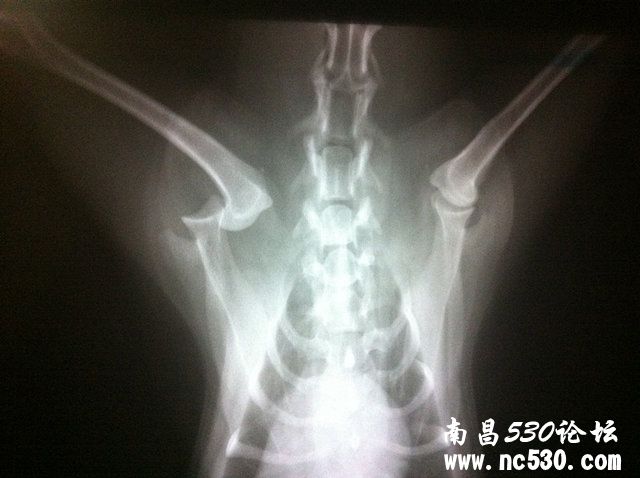

我家狗狗两天前晚上在家里浴室洗澡时,从平台上跳下滑倒摔伤。此后不能正常站立和行走,左前肢不着地。今天去医院拍X光检查,显示左前肢肩关节脱位(如下图)。医生转动前肢和夹脚趾时狗狗均有痛感。请问是否有可能不打开手术,而是手工进行复位后再固定?担心麻醉对狗狗身体伤害太大。多谢医生!

泰迪左前肢肩关节脱位